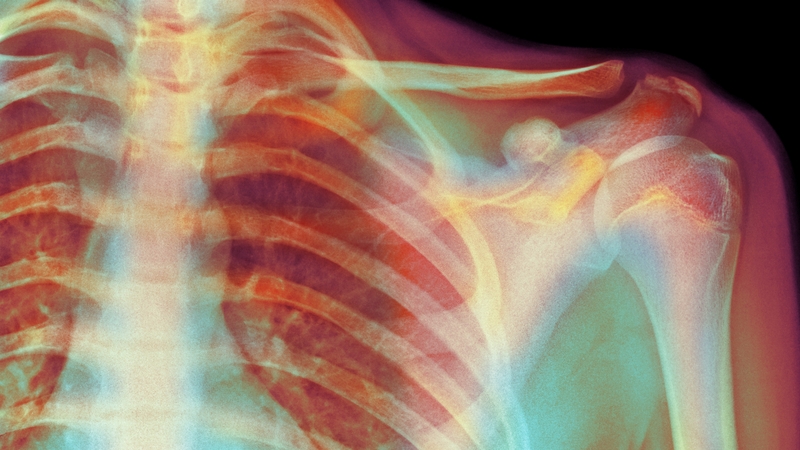

'The relationship between 'damage' on scans and pain is not a straightforward one'. Photo: Getty Images

The belief that torn tendons or worn cartilage are responsible for pain is a key force in driving people's desire to undergo surgery to have the problem fixed. The relationship between 'damage’ on scans and pain is not a straightforward one. If you are in your forties and have an MRI of your knee or shoulder, it will almost certainly show some abnormalities, even if you do not have pain. This makes interpreting scans a challenge, because in many ways they are more a sophisticated calendar of our age, than they are a way to understand pain. Those wrinkles on our faces are mirrored by the ones in our joints!